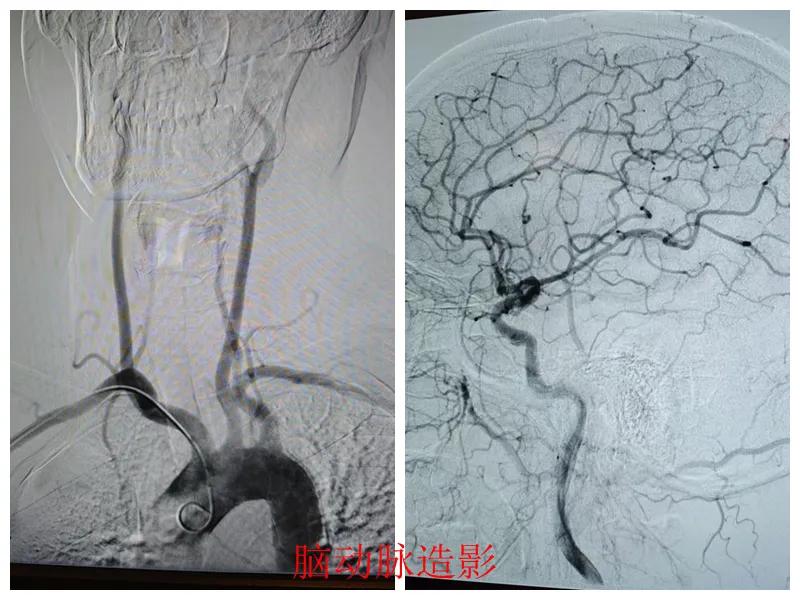

近日,市二院心血管內(nèi)科聯(lián)合介入科為患者成功實(shí)施了“心腦同治”聯(lián)合造影手術(shù),標(biāo)志著醫(yī)院在“心腦同治”介入治療方面取得了顯著進(jìn)展,為同時(shí)合并心腦血管疾病的患者查清了病癥,取得了良好的診療效果。

患者張某,47歲,因胸悶、左上肢麻木20天到市二院心血管內(nèi)科就診,結(jié)合既往冠脈CTA、頭頸聯(lián)合CTA結(jié)果、高血壓病史以及入院后的輔助檢查結(jié)果,診斷為冠狀動(dòng)脈重度狹窄、頸動(dòng)脈狹窄。

經(jīng)王瑾院長(zhǎng)和心血管內(nèi)科、介入科多學(xué)科專家會(huì)診后,決定為患者進(jìn)行冠狀動(dòng)脈和腦血管聯(lián)合造影檢查,一次性完成心腦血管評(píng)估,并同步開展腦血管及冠心病介入治療。

術(shù)前準(zhǔn)備完善后,在王瑾院長(zhǎng)帶領(lǐng)下,心血管內(nèi)科主任李慧新、影像科主任宋貴良、副主任醫(yī)師趙進(jìn)科等緊密協(xié)作,成功為患者實(shí)施了冠狀動(dòng)脈造影及腦動(dòng)脈造影兩項(xiàng)檢查。冠狀動(dòng)脈造影結(jié)果提示:患者右冠狀動(dòng)脈慢性閉塞,腦動(dòng)脈造影提示腦血管多支狹窄病變。

術(shù)后,根據(jù)造影檢查結(jié)果,科室團(tuán)隊(duì)為患者制定了個(gè)體化的治療方案,經(jīng)過一段時(shí)間的規(guī)范化治療,患者很快便康復(fù)出院。